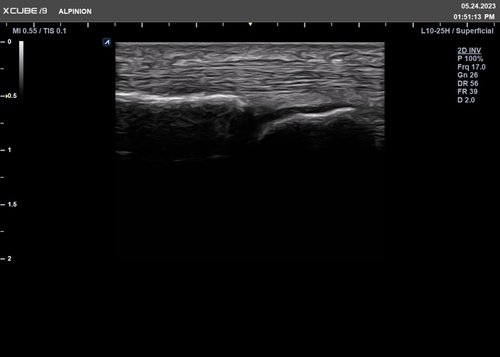

• L10-25H (10-25 MHz) für Ultraschalluntersuchungen in Bereichen MSK, Vaskulär, Weichteile, EM

Für das X-CUBE i9 steht ein umfangreiches Schallkopfportfolio zur Verfügung. Somit kann das komplette internistische Spektrum inklusive der Kardiologie, aber auch Untersuchungen des Bewegungsapparates mit hochauflösenden Schallköpfen bis 25 MHz oder gynäkologische bzw. urologische Untersuchungen mit der Qualität eines Standsystems durchgeführt werden.

Herausragende Bildqualität für vielseitige Diagnostik

Klare Bilder bieten Komfort und Sicherheit bei der Diagnose eines breiten Spektrums von Patienten.

Das X-CUBE i9 ist mit der X + Architektur, innovativen Bildgebungsalgorithmen und einem effizienten Diagnose-Workflow ausgestattet, um die vielfältigen klinischen Anforderungen mit kristallklarer Bildqualität effektiv zu unterstützen.